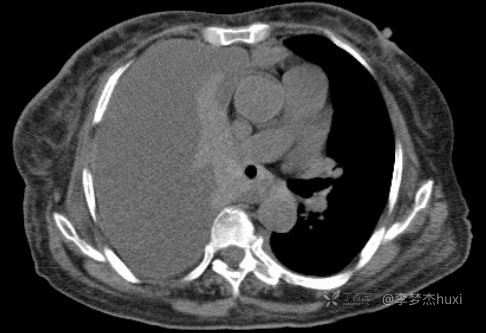

女性78岁,右侧满罐胸水,你绞尽脑汁也想不到的原因

简要病史:患者缘于入院前1个月无明显诱因出现胸闷不适,进行性加重,无明显咳嗽、咳痰,无胸痛及咯血,无喘息,伴进食差,食欲明显减退,无恶心、呕吐,无腹痛、腹泻,伴腰背部疼痛,活动后明显,无尿便失禁,无发热,院外未治疗,来诊

体格检查:T:36.5℃;P:96次/分;R:20次/分;Bp:100/55mmHg,神清,呼吸平稳,浅表淋巴结不大,重度贫血貌,左肺叩清音,右肺叩浊音,右肺呼吸音消失,左肺呼吸音低,未闻及明显啰音,心率96次/分,律齐,无杂音。腹部平坦,软,全腹无压痛,无反跳痛及肌紧张,肝脾肋下未触及,双下肢水肿。

临床诊断:右侧胸腔积液